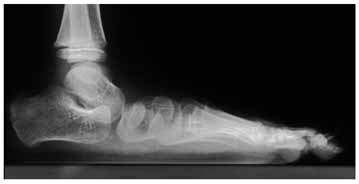

この疾患の構造は、内反足の逆と考えると理解しやすいと思います。簡単に言うと、内反足は、距骨に対しその周囲の骨群が内方かつ下方へ内旋しながらずれているのですが、外反扁平足では、距骨に対しその周囲の骨群は外方かつ上方へ外旋しながらずれています。下の写真は典型的な外反偏平足です。正常足であれば距骨頭(距骨の先端)の正面に舟状骨があるのですが、これが距骨頭の外側に位置をかえていることがわかります。また、側面像で足の骨のアーチが無くなり偏平になっています。

外反偏平足では、距骨とその周囲の骨群との間に不安定性があり、体重をかけると足の前方部分がグニャッとなって外に向いてしまいます。この時、足の内側が突出しますが、こと突出した部分は距骨の頭であり、靴を履いているとこの部分があたって痛みがでることがあります。不安定性がありますので、歩行の時の蹴り出しに力が入らず、走るのが遅く、長距離歩行では疲れやすくなります。